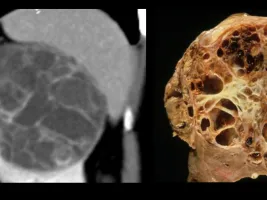

- Characterisation of solid and cystic renal masses

The course covers the main kidney diseases including characterization of cystic and solid renal masses, and other diseases ( vascular, inflammatory, kidney stones, trauma ) as well as kidney CT and MRI protocols.